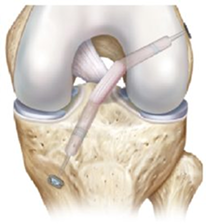

Para mantener su estabilidad, la rodilla tiene los ligamentos cruzados y los ligamentos laterales, los cuales unen el fémur con la tibia.